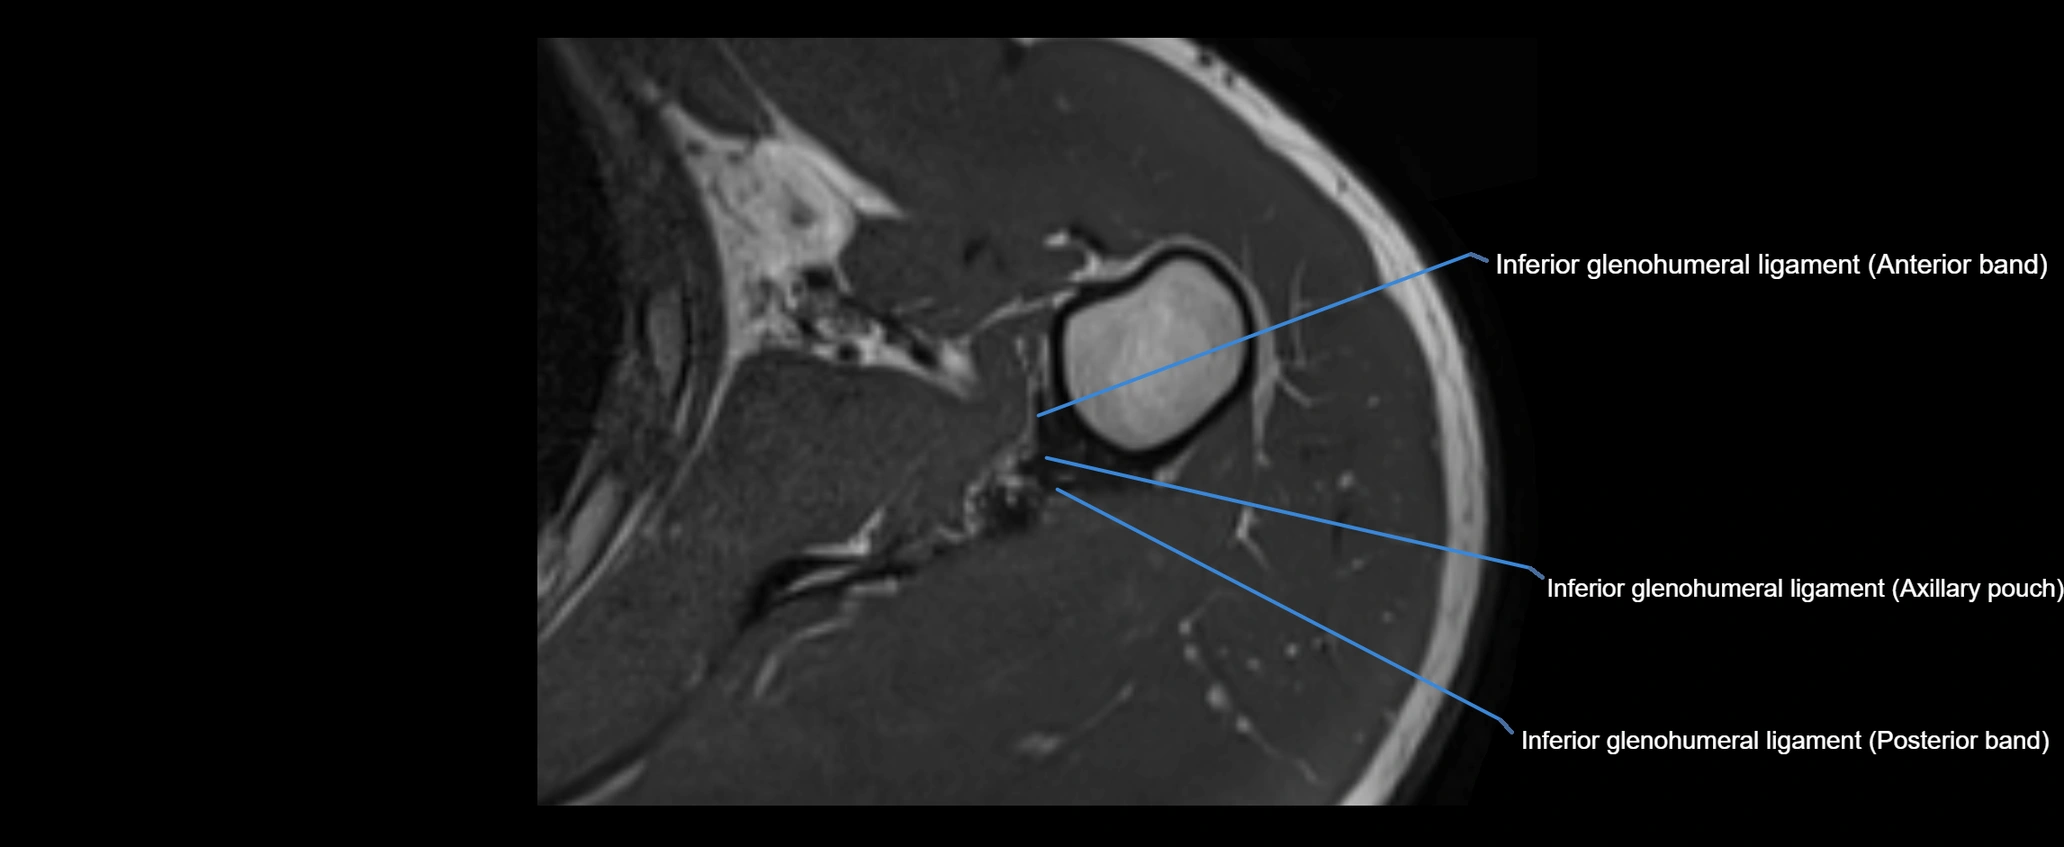

MRI images

image